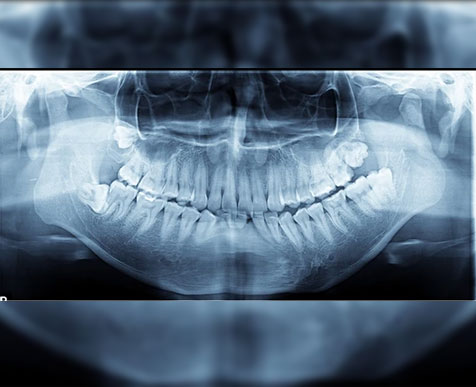

Introducing our AI-powered dental implant planning system that can create preliminary treatment plans in a matter of seconds.

Spending a lot of time in front of your computer planning implants should be a thing of the past. Our AI-powered implant planner helps you achieve more with less, minimizing manual adjustments and maximizing your efficiency throughout the process.

Automatic AI panoramic curve

Automatic AI implant planning